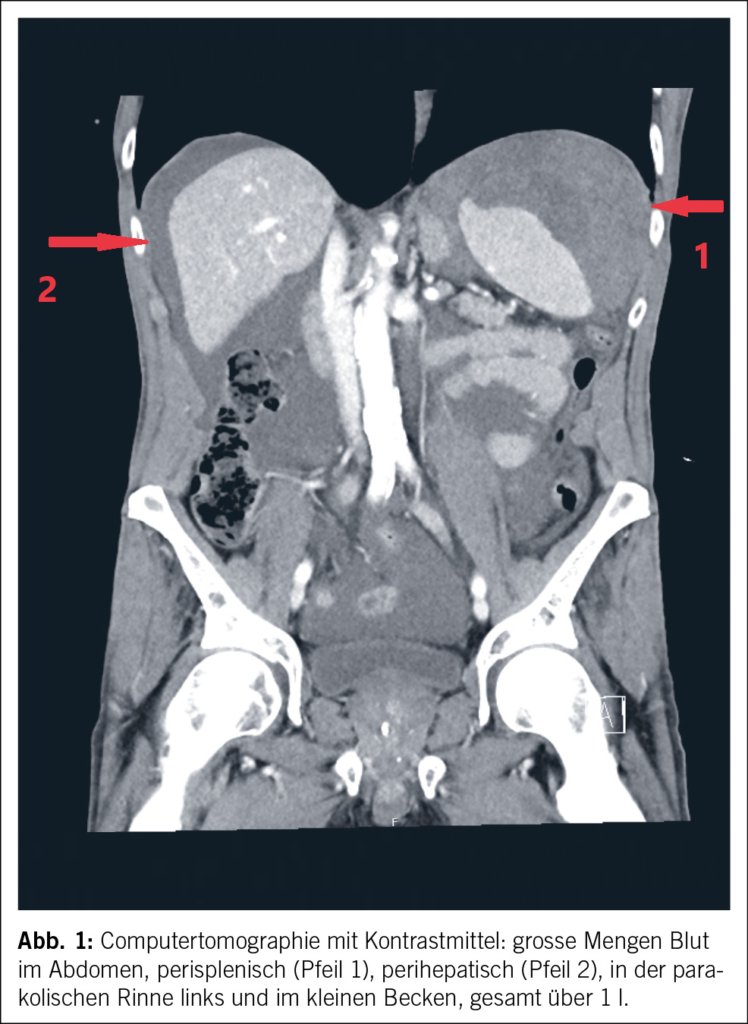

In der Computertomographie (Abb. 1) konnte intraabdominal viel freies Blut dokumentiert werden. Ätiologisch zeigte sich eine Milzblutung mit grossem subkapsulärem Hämatom und eine aktive Blutung der Milz in die Bauchhöhle (Abb. 2 und 3), entsprechend einer Verletzung Grad IV nach der American Association for the Surgery of Trauma (AAST) grading scale for splenic lacerations (7). Diese Einteilung richtet sich nach der Grösse des subkapsulären Hämatoms, dem Vorhandensein eines Kapselrisses, dem Ausmass der Organlazeration und dem Vorhandensein einer aktiven Blutung.